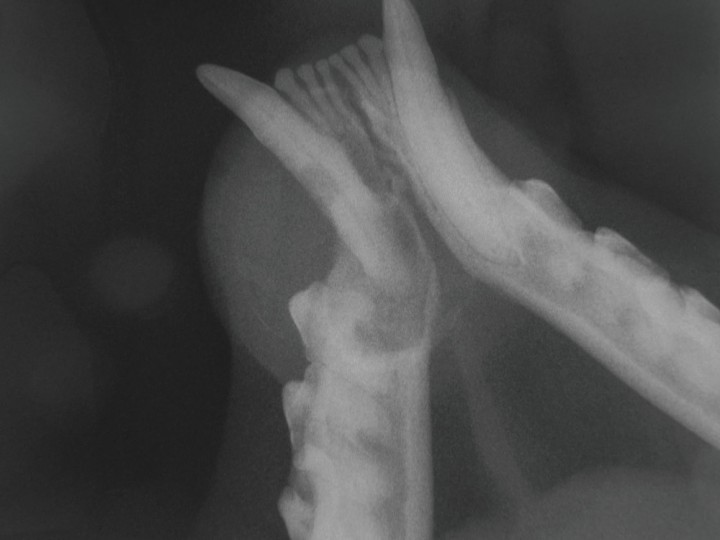

En la radiografía dental oclusal de los caninos mandibulares (Fig. 3) se observó una imagen compatible con lesión reabsortiva en el tercio coronal de la raíz del 304, junto con una zona radiolúcida compatible con una osteolisis severa en el área periapical de este canino. Se apreció una moderada reabsorción radicular en la región apical del 304, no pudiendo determinar si la lesión era debida a la presencia de una reabsorción dental o a la patología periapical asociada.

<p>Radiografía dental oclusal de los caninos mandibulares. Se observa una imagen compatible con lesión reabsortiva en el tercio coronal de la raíz del 304 junto con una zona radiolúcida compatible con una osteolisis severa en el área periapical de este canino. Se aprecia una moderada reabsorción radicular en la región apical del 304.</p>

Radiografía dental oclusal de los caninos mandibulares. Se observa una imagen compatible con lesión reabsortiva en el tercio coronal de la raíz del 304 junto con una zona radiolúcida compatible con una osteolisis severa en el área periapical de este canino. Se aprecia una moderada reabsorción radicular en la región apical del 304.

Finalmente se observó una pérdida de hueso vertical, asociada probablemente con la lesión endoperiodontal tipo 1 que padecía el paciente. Se puede concluir con cierta seguridad que tras afectarse la pulpa, consecuencia de una lesión reabsortiva presente en el tercio coronal de la raíz del 304, se produjo una afección pulpar, posiblemente de origen bacteriano que, tras producir una necrosis pulpar, migró a través del delta apical hasta el ligamento periodontal, produciendo una enfermedad periodontal. De esta forma confirmamos radiológicamente lo que la sonda periodontal nos había indicado en la exploración oral previa.

Estas lesiones, observadas mediante la radiología oral, explican la presencia del absceso dental que provoca la inflamación y la presencia de material purulento en la citología anteriormente mencionada.

La lesión reabsortiva presente en 304 la podemos clasificar como clase 3, tipo 3. La clasificaremos clase 3 (según la clasificación de la AVDC de las reabsorciones dentales felinas por su gravedad y localización),[ AVDC board. Veterinary Dental Nomenclature. Recommendations from the AVDC Nomenclature Committee adopted by the American Dental College Board. Most recently updated May 2012. [AVDC] ] ya que podemos observar una pérdida profunda de tejido duro dental en la superficie bucal del tercio coronal de la raíz del 304, apreciándose que la lesión se extiende a la cavidad pulpar y que la mayor parte del diente conserva su integridad. La clasificaremos como tipo 3 (según la clasificación del AVDC de las reabsorciones dentales felinas por la imagen radiológica)[ AVDC board. Veterinary Dental Nomenclature. Recommendations from the AVDC Nomenclature Committee adopted by the American Dental College Board. Most recently updated May 2012. [AVDC] ] porque además de observar la lesión focal radiolúcida antes mencionada, también se aprecia una disminución de la radiopacidad de parte del diente localizada en la porción apical de la raíz de 304, caracterizada por la pérdida del espacio ocupado por el ligamento periodontal.[ Lyon KF, Visser CJ, Okuda A, Anthony JMG: Feline stomatitis syndrome, periodontal disease, and feline odontoclastic resortive lesions. En: An Atlas of Veterinary Dental Radiology. Iowa State University Press, Ames 2008; 177-198. , Dupont GA, DeBowes LJ. Tooth Resorption. En: Atlas of Dental Radiography in Dogs and Cats: A Practical Guide to Techniques and Interpretation. Ed. Saunders, Elsevier Inc. St. Louis, Missouri 2009; 172-181. ]